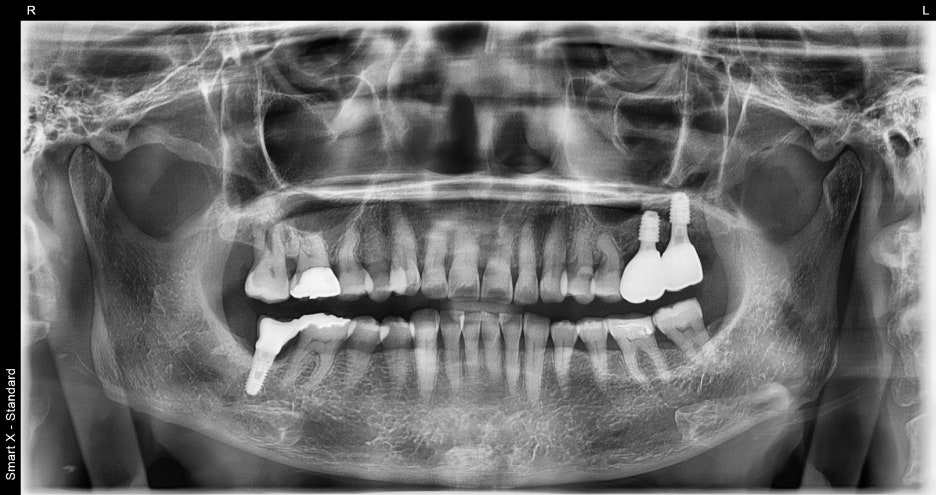

At the first visit

At Seoul Orbit Dental Hospital, we take a 3D CT scan before all implant treatments.

In this case, we found:

Severe bone loss around #26 and #27

The maxillary sinus had descended significantly

Inflammation between the root and the gum

Based on the panoramic X-ray and intraoral photos,

we diagnosed the following:

The two upper left molars were fractured and missing

The surrounding alveolar bone was relatively healthy, so implant placement was possible with minimal bone grafting